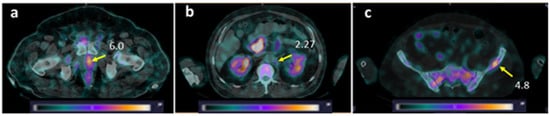

Figure 5. Decrease in tissue uptake (SUVmax) in primary tumor (upper panel, Patient 7), LNM (middle panel, Patient 13, paraaortic lymph node), and BM (bottom panel, Patient 10) with time. Yellow arrow—lesion; red arrow (middle panel)—dilated left ureter. A linear relative scale (normalized at the maximum activity in the image, SUVmax, from 0 to 5.0) is applied.

The activity uptake in primary lesions has a tendency to be higher after administration of [99mTc]Tc-DB8, corresponding to 120 µg peptide mass; however, the difference was statistically significant only at 4 h pi between uptakes after injections of 120 µg and 80 µg (Figure 3c). The activity uptake in primary lesions did not correlate with PSA concentrations in the blood, tumor size, or castration resistance. However, there was a tendency toward lower tumor uptake with increasing GS, determined by pathology examination (Figure 6). The image contrast (tumor-to-surrounding tissue SUVmean ratios) increased with time, a finding that was more pronounced for the group injected with the lowest peptide mass (Table 3).

LNMs were visualized in 2 out of 12 patients with known lesions (16.7%), and BMs in 2 out of 6 patients with known lesions (33.3%) (Figure 7). Additionally, activity uptake in BMs was visualized in two patients without known bone involvement according to CT. Patients with visualized LNMs and BMs were administered 80 or 120 µg of peptide. The SUVmax values for LNMs and surrounding tissues for individual patients were lower than for primary tumors in both groups injected with 80 and 120 µg of peptide, while for BMs, the group injected with 80 µg had a higher SUVmax than for primary tumors (Table 1). Nevertheless, the ratios for SUVmean in metastatic lesions to surrounding tissues were suitable for visualization: for LNM, 1.97–3.49 for 80 µg and 2.40–2.61 for 120 µg; for BM, 3.97–9.81 and 1.72–2.53, respectively.

Figure 7. SPECT/CT images of PCa patients 2 h after injection of [99mTc]Tc-DB8. The foci of increased [99mTc]Tc-DB8 uptake (yellow arrow, SUVmax) are visualized (a) in the prostate (Patient 16); (b) in the paraaortic lymph node on the left (Patient 10); and (c) in the left ilium (Patient 10). A linear relative scale (normalized at the maximum activity in the image SUVmax from 0 to 5.0) is applied.